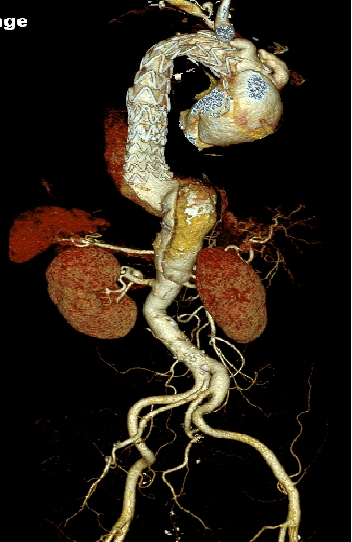

男,49岁,急性AD。2019年1月TEVAR,3月RTAD,行全弓置换+支架象鼻。2022 年1月25日术后复查,结果良好。